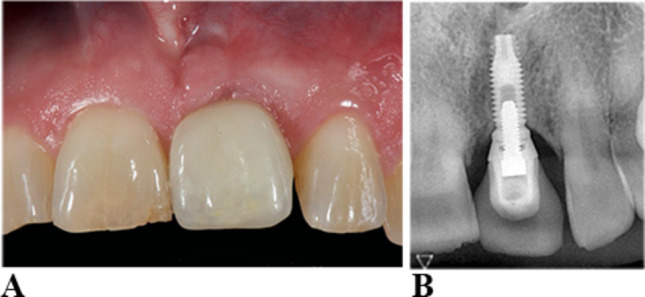

Methods: Implant-supported single crowns and bridges were used to rehabilitate 162 implants in 57 patients. Patients were examined over a 2 to 20-year period on a recall schedule of 3 to 6 months. In addition to recording clinical parameters, intraoral radiographs were taken at baseline (immediately after superstructure insertion) and at 1, 3, 5, 10, 15, and 20 years. Patients were differentiated into phenotype 1 with thin, scalloped gingiva and narrow attached gingiva (n = 19), phenotype 2 with thick, flat gingiva and wide attached gingiva (n = 23), or phenotyp 3 with thick, scalloped gingiva and narrow attached gingiva (n = 15).

Abstract Image